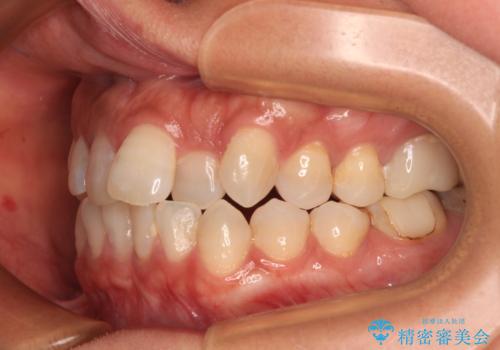

クロスバイトを治したい インビザラインによる矯正治療

- 前歯のクロスバイトを気にして来院された患者様です。

上下ともに、前歯部を中心にやや叢生が認められる程度であったため、ワイヤーでもインビザラインでも、どちらでも対応可能な状態でした。

咬合力が非常に強く、治療が進むにつれて上下奥歯が離開してくることが予想されるため、治療途中から上下の顎間ゴムを使用することを理解いただき、インビザラインによる矯正治療を行うこととしました。